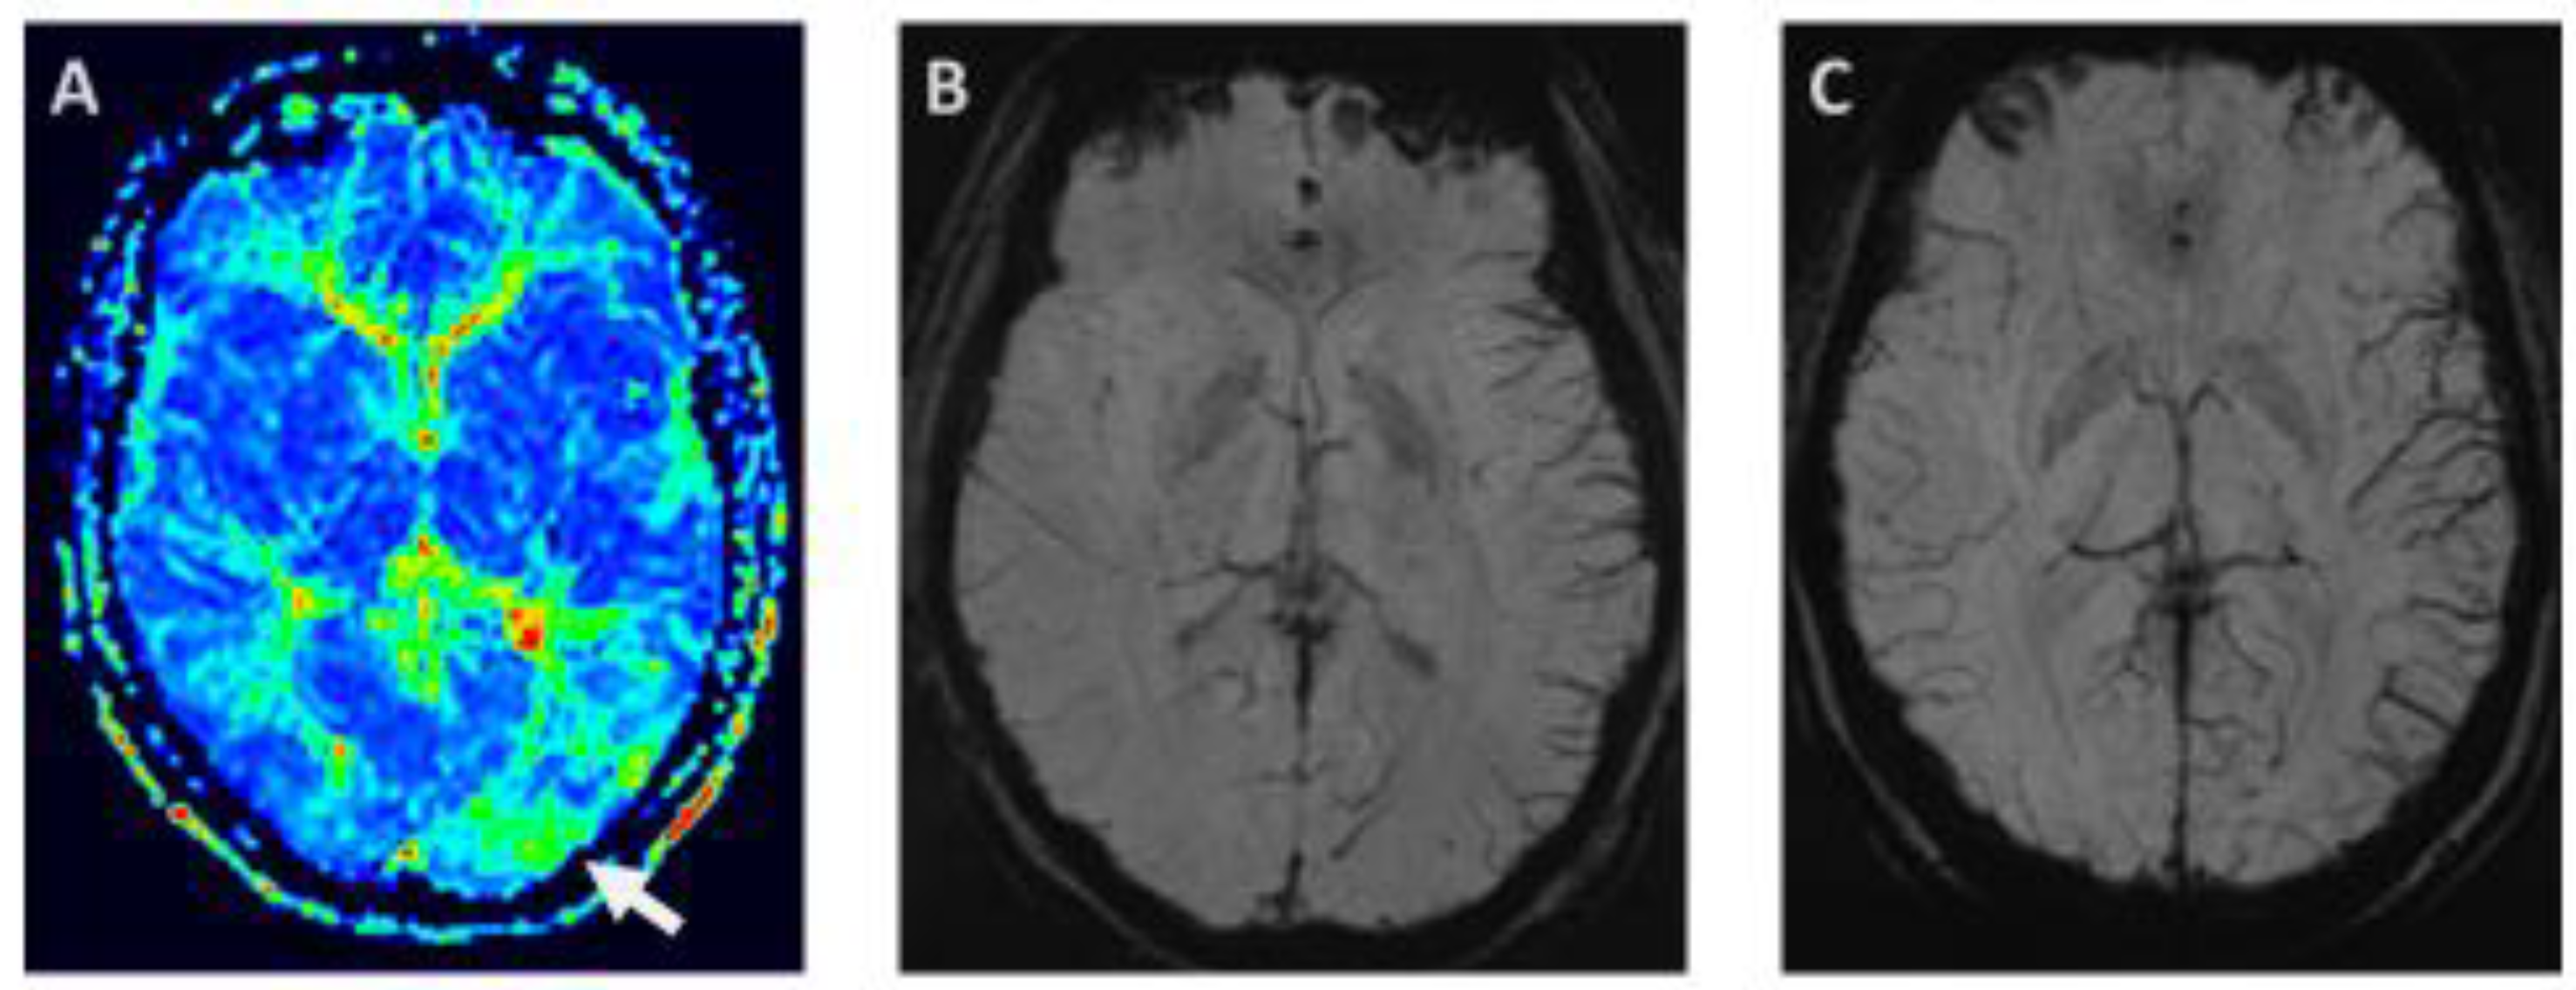

- Kellner-Weldon, F.; Jossen, M.; Breiding, P.S.; Grunder, L.; Schankin, C.; Scutelnic, A.; Fischer, U.; Muri, R.; Pastore-Wapp, M.; Wiest, R.; et al. Imaging Neurovascular Uncoupling in Acute Migraine with Aura with Susceptibility Weighted Imaging. Clin. Neuroradiol. 2021, 31, 581–588. [Google Scholar] [CrossRef]

- Slavova, N.; Denier, N.; El-Koussy, M.; Wiest, R.; Kellner-Weldon, F.; Fischer, U.; Schankin, C.J. The index vein pointing to the origin of the migraine aura symptom: A case series. Neurology 2020, 94, e2577–e2580. [Google Scholar] [CrossRef] [PubMed]

- Scutelnic, A.; Petroulia, V.; Schraml, L.; Jung, S.; Branca, M.; Beyeler, M.; Fischer, U.; Wiest, R.; Slavova, N.; Schankin, C.J. The “index vein” as a sign for migraine aura in the emergency setting. Cephalalgia 2023, 43, 3331024221132010. [Google Scholar] [CrossRef]